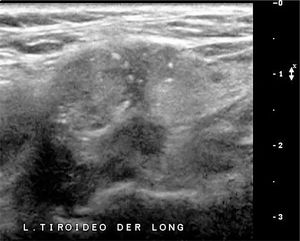

SIGNOS ECOGRÁFICOS DE MALIGNIDAD DE LOS NÓDULOS TIROIDEOSLas características ecográficas de los nódulos que sugieren malignidad son: nódulo sólido hipoecogénico o marcadamente hipoecogénico, más alto que ancho, de bordes irregulares, microlobulados o espiculados y con microcalcificaciones (Figura 7a, 7b, 7c y 7d). La heterogeneidad no es un signo específico, lo mismo para la naturaleza sólida. Los contornos mal definidos tampoco. La hipoecogenicidad en nódulos menores de 10mm tiene menor valor predictivo positivo que en nódulos de más de 10 mm3. Las calcificaciones a modo de cápsula tienen alta especificidad cuando se encuentran asociadas a un nódulo que claramente las rebasa (Figura 8). Considerando sólo el tamaño de los nódulos, se sugiere puncionar los nódulos sólidos mayores de 10mm de diámetro y los sólido-quísticos mayores de 20mm. Mientras más criterios de malignidad presenta el nódulo, mayor será la probabilidad de malignidad3,4,8,9,12.

Nódulos tiroideos con caracteres ecográficos de malignidad.

A: Nódulo tiroideo sólido, marcadamente hipoecogénico, además presenta microcalcificaciones en la periferia (Ca papilar).

B: Nódulo tiroideo sólido más alto que ancho: diámetro anteroposterior (alto) mayor que el diámetro longitudinal (ancho). (Ca papilar).

C: Nódulo tiroideo sólido, en un corte transversal, adyacente a la arteria carótida común, de contornos microlobulados, hipoecogénico y heterogéneo. (Ca papilar).

D: Nódulo tiroideo sólido, con microcalcificaciones en el interior y periferia. (Ca papilar).